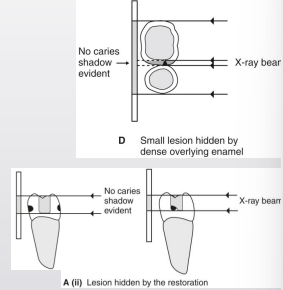

how is horizontal angulation a limitation of 2D imaging

change in angulation impacts ability to detect and stage carious lesions

what is horizontal angulation

contact overlap can obscure lesion and DEJ

changes of lesions relative to other structures→ DEJ and pulp

why is too much vertical angulation not a good thing

if looking at restorations particularly, if the angle is big → decay will be hidden under restoration